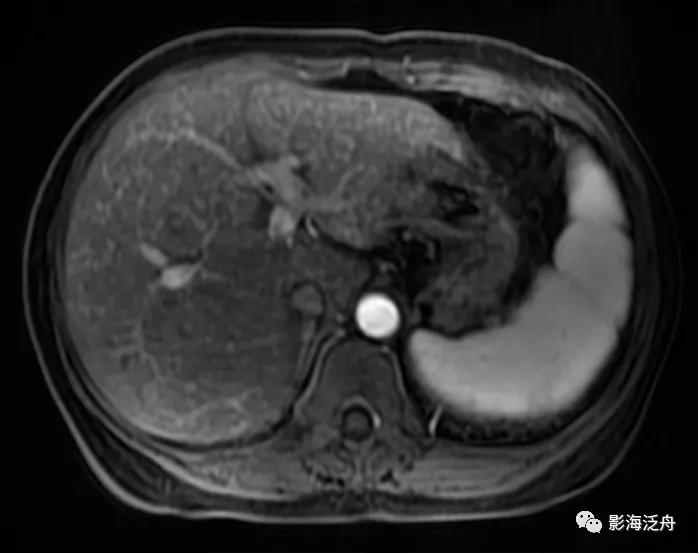

中年女性患者,皮肤黄染、瘙痒一月余前来就诊。能从这幅图像上发现什么问题吗?

将正常人与该患者的T2WI抑脂序列放在一起对比观察。在抑脂较均匀的区域,可以发现该患者肝实质的T2WI信号轻度增高(红箭),门静脉周围的胆管间隙增宽(绿箭),肝周间隙缩小(蓝箭)提示肝脏肿大,脾大(黄箭)。

上图特征不甚明显,需要反复对比观察。

增强动脉期,患者肝实质呈弥漫性斑点状强化(类似于粟粒型肺结核),这种强化方式可能与动脉及门脉的细小分支异常分流及部分肝组织灌注不良有关。门脉期及静脉期患者肝实质呈较均匀强化(未给出图像),提示病程相对可逆。

与正常人对比可以更好地观察上述图像特征,注意肝损伤患者的肝脏强化程度整体较低(以脾脏强化程度作为参照,两幅图像的强化时间大致相仿),但平衡期强化程度并无异常减低(未给出图像)。